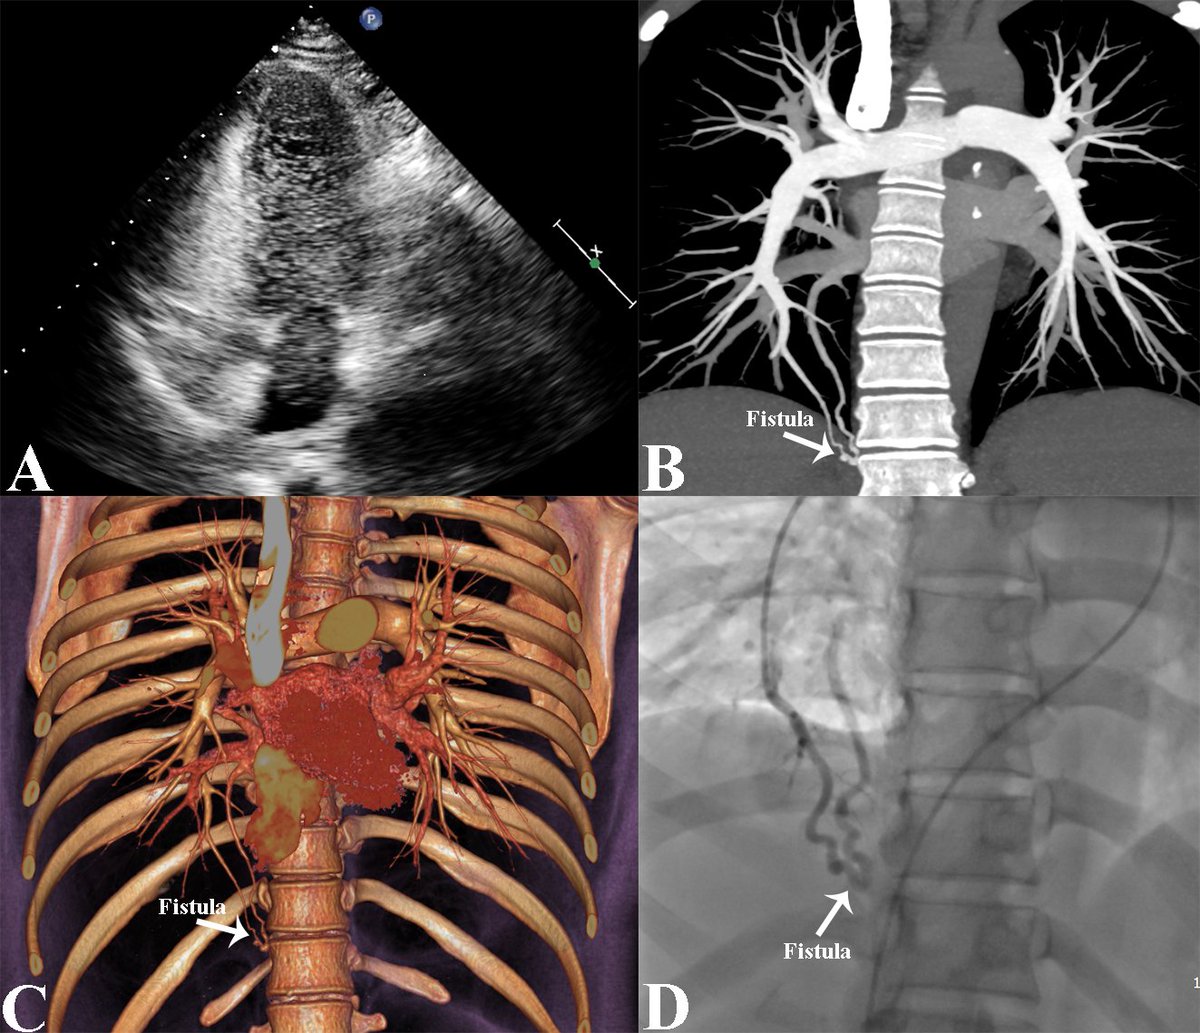

#RCA CTO #HDR #TDADR #CBfenestration @OpolskiMP Warsaw CTO case 7Fr TDADR with B.C.anchoring UB3→#HDR→IP→XT nontip →2nd →Type 2B→XT non TIP→3rd HDR→XT→Contrast injection show DTL→GW was not crossed→#CB like #SAFER →sionblack was not crossed→#TDADR with